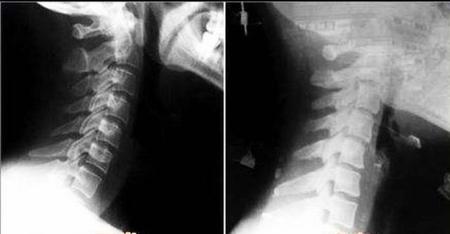

颈椎病主要两个发病原因一个是长期久坐使用电脑手机,另一个就是睡姿问题。下图就是颈椎病生理曲度变直,和正常颈椎的x线图片。